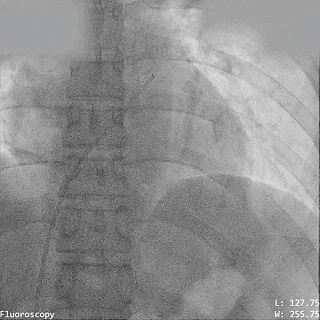

右心导管检查明确肺动脉压力

导丝过隔

PannaWire多功能导丝“让过隔更简单”

选择1224S规格导丝过缺损,PannaWire多功能导丝配合MPA导管通过ASD送至左心房